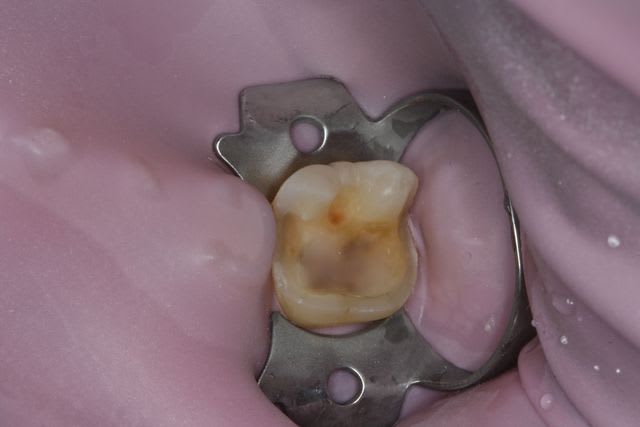

Un petit onlay du dimanche dernier qui m'a fait plaisir. A souligner le travail du prothésiste, content de son boulot après avoir vu les photos.

La cavité d'accès pour une dévit est insuffisante , la dent est vivante . La limite de la cavité est sus gingivale .

Dent vitale. Il y avait un compo OD et le pan V a lâcher. Limite supra-gingivale.

Ci joint une autre vue.